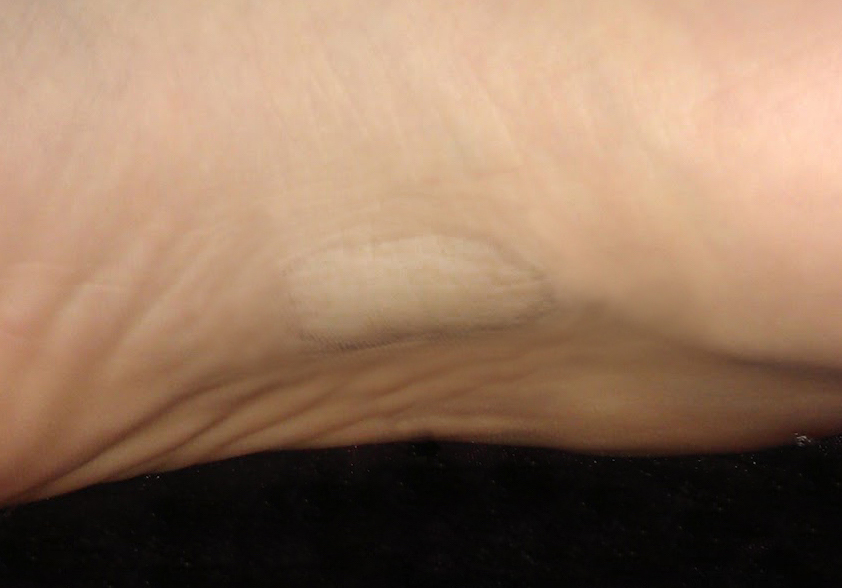

Si has encontrado un bulto en el arco plantar, es muy probable que haya desarrollado un fibroma plantar (también conocido como fibromatosis plantar cuando se desarrollan en conjunto). Esta patología se encuentra enmarcada dentro de la enfermedad de Ledderhose y es un crecimiento anormal de la fascia plantar acompañado con un crecimiento benigno o nodular, afectando con mayor frecuencia a varones.

Los fibromas por si solos no causan dolor, es la presión directa sobre el fibroma la que puede dar lugar a dolor en arco plantar cuando caminamos, estamos de pie o en la práctica deportiva. Normalmente los síntomas se describen como sensación de cuerpo extraño en la planta del pie (como una piedra dentro del calzado) cuando traccionamos la fascia plantar.